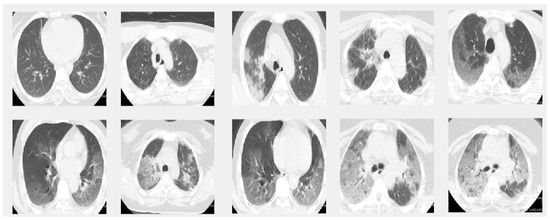

In this paper we used two different datasets which are available online. The first dataset is on chest X-ray images (see Figure 1) and the second on CT scans of lungs (see Figure 2).

Figure 2. Sample images from the CT dataset. The images in the first row give 5 sample slice images about 0–10–20–30–40% COVID-19 infection in the lungs and the second rows show 50–60–70–80–90% respectively.